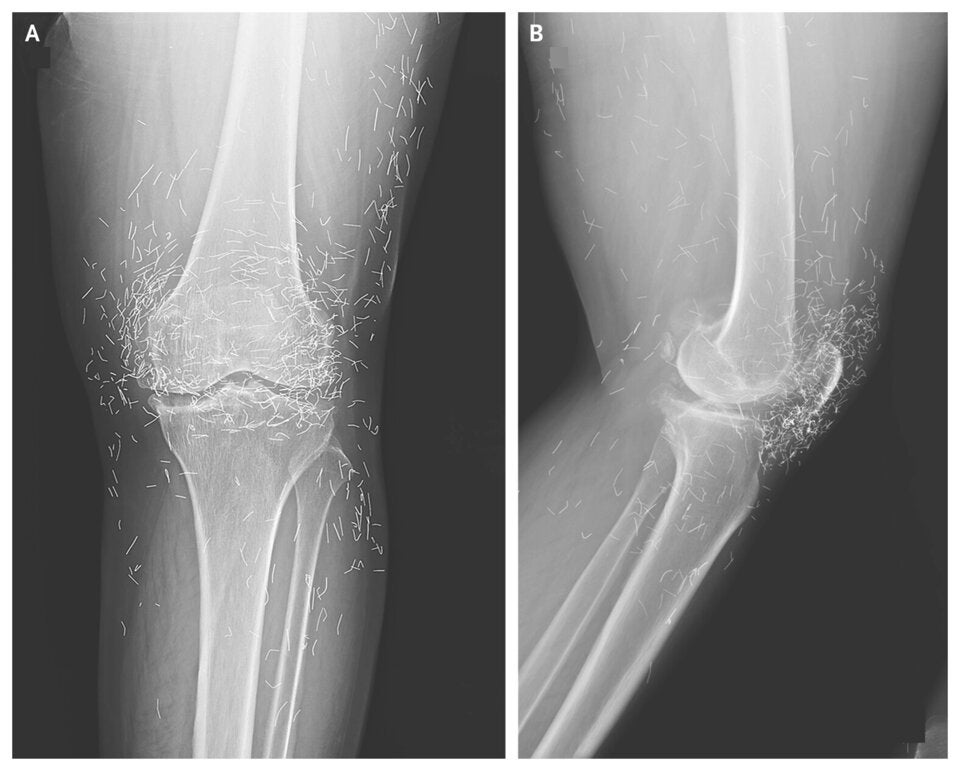

Röntgenaufnahme eines Knies mit auffälligen Fremdkörpern im Gewebe – Ärzte fanden Hunderte winzige Goldfäden.

© New England Journal of Medicine

Die Ärzte stellten nicht nur die typischen Anzeichen einer fortgeschrittenen Arthrose fest – also knöcherne Verdickungen und Verhärtungen –, sondern auch mehrere hundert winzige Goldfäden im Gewebe rund um das Knie. Die Fachleute warnten, dass diese Methode nicht nur ohne nachgewiesenen Nutzen sei, sondern auch gefährlich sein könne.

Die Fäden können im Körper wandern, Zysten verursachen und Gewebe schädigen. Besonders kritisch: Bei einer Magnetresonanztomografie (MRT) können sie verrutschen und Blutgefäße verletzen. Damit wird eine wichtige Untersuchung, die Leben retten kann, erschwert oder sogar unmöglich.